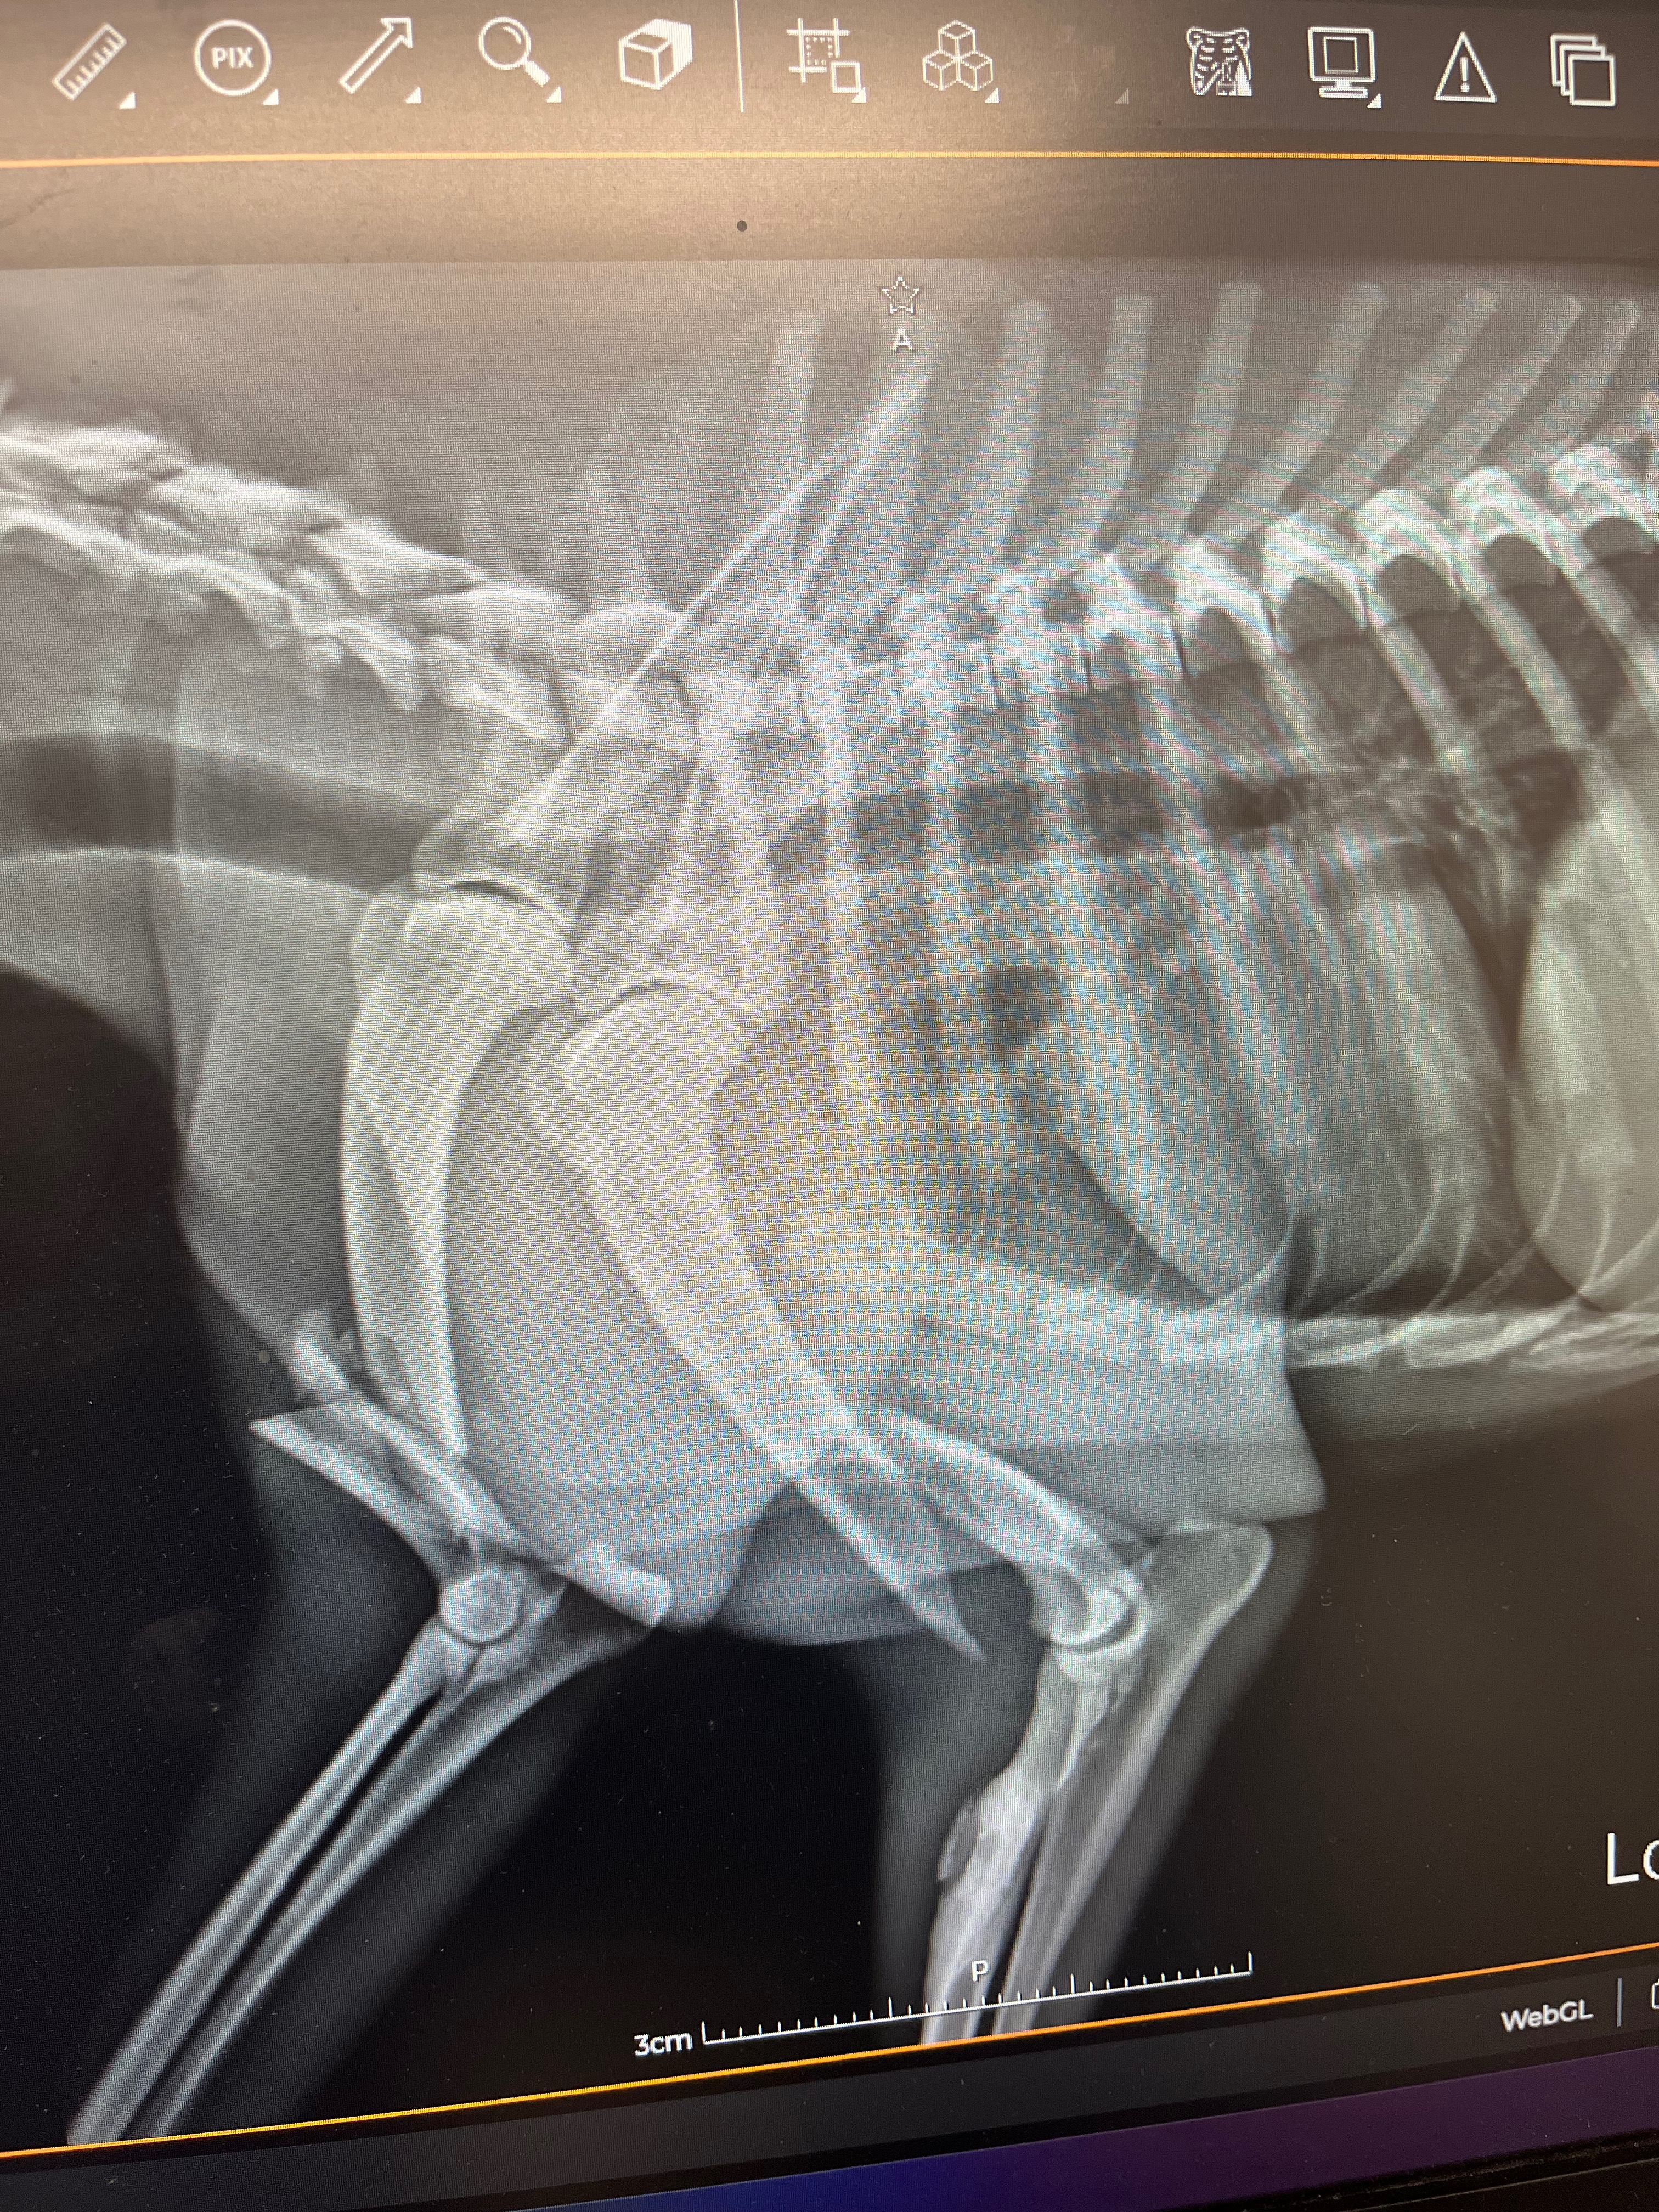

Lo subí a mi coche y lo llevé a la veterinaria. Ahí confirmaron que tiene fractura en ambas patas delanteras y necesita cirugía lo antes posible para poder volver a caminar.